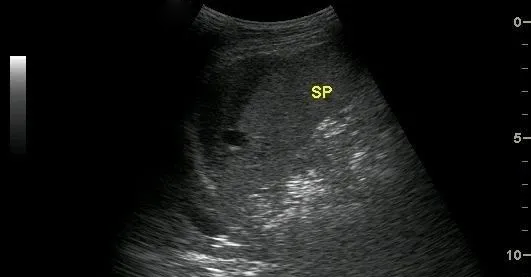

超聲表現(xiàn)為:脾臟實質(zhì)內(nèi)探及邊界清楚的非均質(zhì)區(qū),單發(fā)或多發(fā),如伴有較大血腫時,非均質(zhì)區(qū)內(nèi)可探及不規(guī)則或類圓形無回聲區(qū),透聲較差。